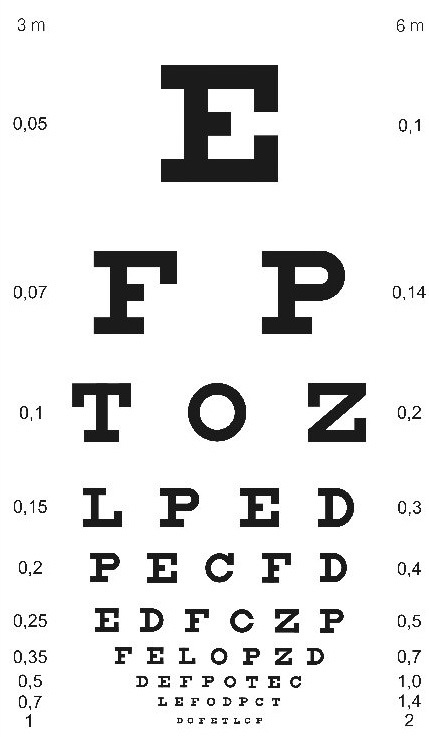

A sonolência excessiva diurna tem sido cada vez mais pesquisada pois é reconhecido seu potencial de comprometimento do desempenho no trabalho e como fator causal em acidentes no trabalho e no trânsito. Sonolência diurna é encontrada em diversas patologias como apnéia obstrutiva do sono e narcolepsia; está largamente presente na população urbana com privação parcial e crônica de sono, bem como nos trabalhadores em turnos. A Escala de Sonolência Epworth é um questionário preenchido pelo próprio paciente, cujo objetivo é a determinação de uma medida geral do grau de sonolência diurna, em adultos. Após preenchido o médico neurologista analisa e fornece uma pontuação conforme as resposta do questionário pelo paciente, quantificando sua sonolência em situações monótonas, da vida diária. A principal superioridade da Escala de Sonolência EPWORTH é sua aplicação simples, rápida, possibilitando utilização em estudos populacionais principalmente em pessoas que trabalham em altura, motoristas de ônibus e caminhões, favorecendo a busca por apnéia obstrutiva do sono.

A Escala de sonolência Epworth sugere a possibilidade de algum distúrbio do sono (insônia, sonambulismo, etc.) que durante a noite impede o paciente de ter um sono tranqüilo, reparador e consequentemente provoca sonolência durante o dia prejudicando suas atividades.

A hipersonolência diurna é uma das manifestações mais relevantes da síndrome da apneia obstrutiva do sono e pode ser avaliada quer por testes subjetivos quer por testes objetivos. A escala de sonolência Epworth é um instrumento simples e validado que permite avaliar a sonolência diurna no contexto clínico de distúrbios do sono. No entanto, o seu caráter subjetivo pode condicionar a exata expressão do verdadeiro grau de sonolência. O uso clínico deste questionário é de grande importância na filtragem de trabalhadores onde demanda grande atenção.

Na apnéia obstrutiva do sono a sonolência diurna é um sintoma frequente, mas muitas vezes não é reconhecida, sendo a Escala de sonolência EPWORTH o método mais amplamente utilizado para a avaliação subjetiva da gravidade da sonolência.

O CONTRAN (Conselho Nacional de Trânsito) em sua RESOLUÇÃO Nº 425 contempla a obrigatoriedade da realização da escala de sonolência EPWORTH. Tenha agora em sua clínica a Escala de Sonolência EPWORTH e ofereça a seus clientes de medicina ocupacional mais este exame.